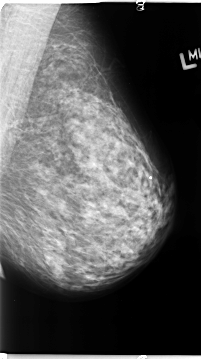

B_3133_1.LEFT_CC

LEFT_CC LINES 4712 PIXELS_PER_LINE 2600 BITS_PER_PIXEL 12 RESOLUTION 50 NON_OVERLAY